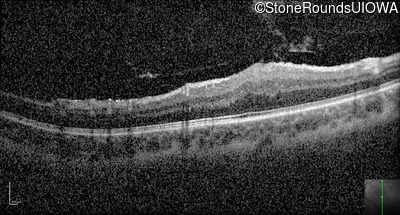

Optical Coherence Tomography - Left - 20/80

Exemplar / OCT Stack